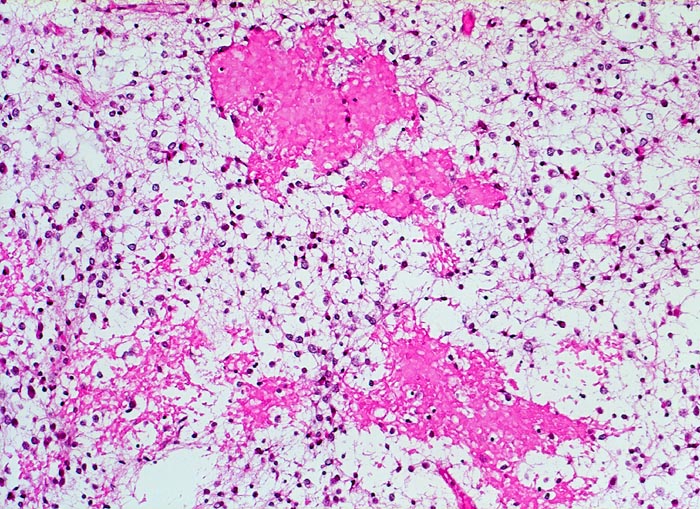

Histologisch bestehen die Oligodendrogliome aus kompakten Aggregaten runder Zellen mit deutlichen Zellgrenzen und klarem Zytoplasmasaum um einen dichten runden zentralen Kern (“Spiegelei”). Die Vakuolisierung des Zytoplasma stellt einen Fixationsartefakt dar und fällt bei Schnellschnitten als diagnostisches Hilfsmittel weg (Gefrierschnitt!). Charakteristisch sind verzweigte Kapillaren. Die Tumorzellen infiltrieren die Hirnrinde diffus und können sich bis in die Meningen ausbreiten.

• Fokale mukoide/zystische Degeneration innerhalb des Tumors mit Ausbildung von Pseudozysten.

• Dichtes Netzwerk verzweigender Kapillaren.

• Tumorzellen umgeben von einem Halo ("Spiegeleier").

• Die Tumorzellen erinnern an Oligodendrozyten der weissen Substanz, haben aber deutlich grössere Kerne.

• Im Gegensatz zum Glioblastoma multiforme monomorphes Zellbild.